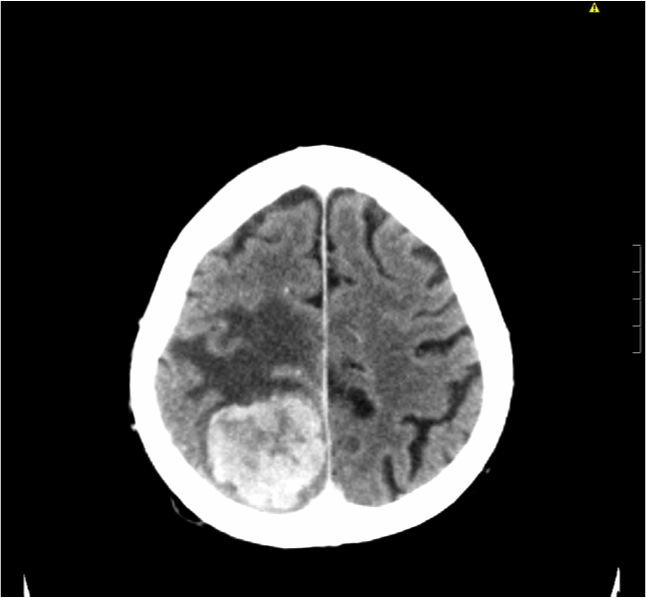

La disartria infantil es definida como una alteración neurológica que afecta principalmente la articulación del habla. Comúnmente se confunde con la afasia de broca, que consiste en la incapacidad para ejecutar las órdenes motoras necesarias para el lenguaje oral, al estar afectada el área de broca del cerebro, en el hemisferio izquierdo. Un neuropatólogo y un terapeuta del habla. La disartria causada por un accidente cerebrovascular o lesión cerebral no empeorará y puede mejorar. En la actualidad, existen muchos tipos de disartria, por diferentes razones o según una base diferente de otras. La dicción puede mejorar con terapia del lenguaje y el tratamiento de la causa de base. • disartria por trastornos de múltiples sistemas motores por las características sintomatológicas: Te explicamos al detalle sus síntomas y te ofrecemos recomendaciones claves para su manejo. Depende del patrón de problemas que se observen. Para diferenciar estas tres patologías debemos de tener en cuenta: Hacen referencia a la reducción de las sílabas y pueden manifestarse en distintos contextos como la omisión de consonantes finales, la omisión de sílabas átonas, las reduplicaciones y la reducción de varios grupos consonánticos en uno solo. Si tienes disartria, es posible que tengas dificultad para mover los músculos de la boca, de la cara y del sistema respiratorio superior que controlan el habla. Diagnostico de disartria pseudobulbar el diagnóstico de la disartria pseudobulbar se lleva a cabo durante el examen de los pacientes por un neurólogo, y las posibilidades del aparato articulatorio (después del diagnóstico) son evaluadas por un logopeda.